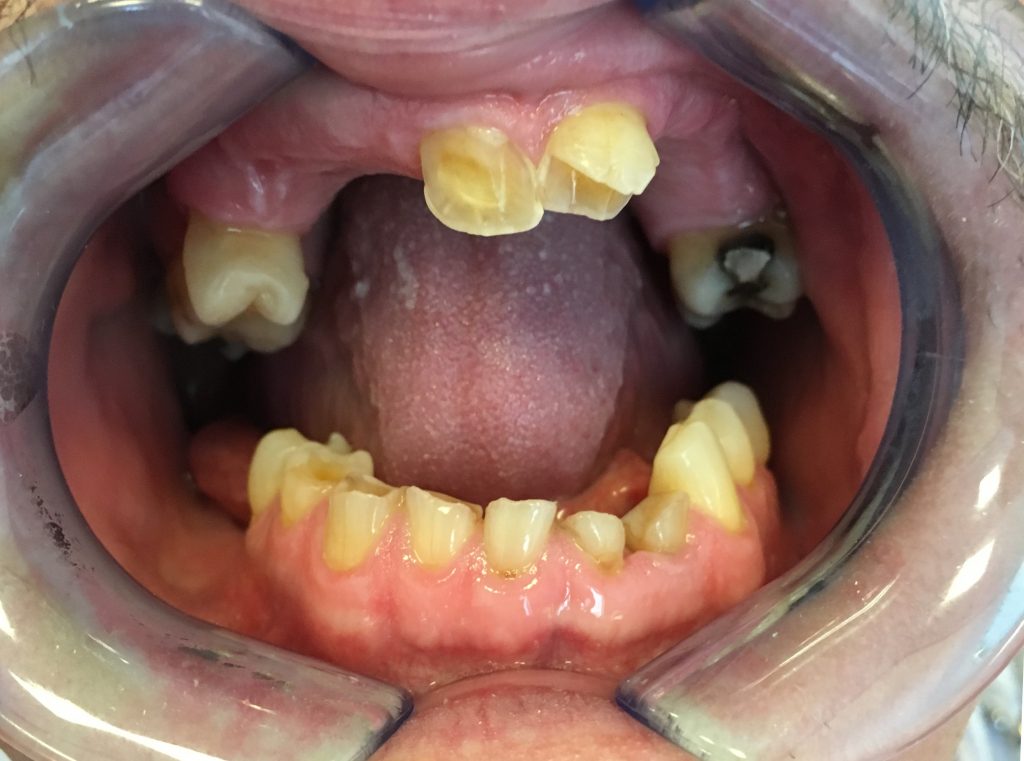

Streszczenie: W pracy podano definicje patologicznego starcia zębów. Na podstawie wybranego piśmiennictwa podano aktualne poglądy na temat: zasad terapii, monitorowania, profilaktyki i opieki następczej nad zrehabilitowanym pacjentem. Podano cztery założenia, według których należy przeprowadzać proces terapeutyczny. Nakreślono sytuacje kliniczne, które wymagają postępowania dwuetapowego. W opisywanym przypadku klinicznym przedstawiono kompleksowe leczenie zaawansowanej atrycji połączonej z niepełnym uzębieniem. Proces leczenia przebiegał dwuetapowo. W pierwszej fazie wykorzystano zgryz konstrukcyjny i diagnostyczne nawoskowanie zębów w celu zapewnienia estetyki. W finalnej fazie odtworzono uzębienie w sposób stały z wykorzystaniem materiałów kompozytowych i koron protetycznych opartych na wkładach koronowo-korzeniowych i protez szkieletowych.

Summary: In the paper, pathological tooth wear is defined. Based on the selected literature, current views on the principles of therapy, monitoring, prevention and aftercare of a rehabilitated patient are presented. Four assumptions have been made according to which the therapeutic process should be carried [...]